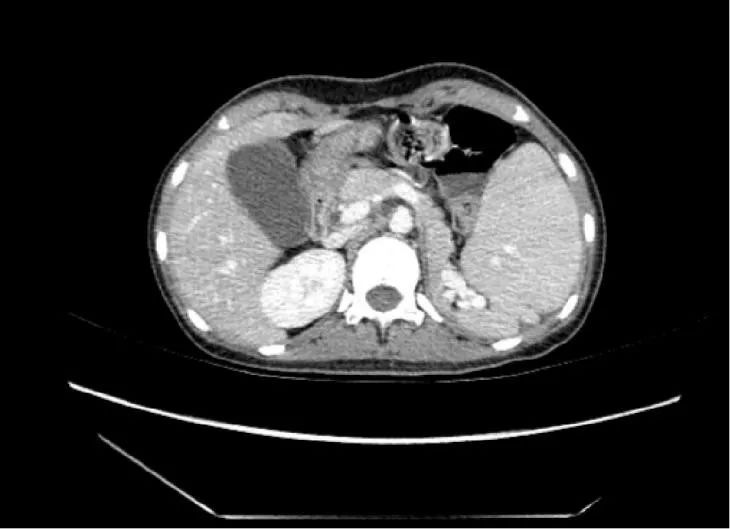

ct平扫轴位图,脾增大,脾实质内见楔形低密度,尖端指向脾门;b.